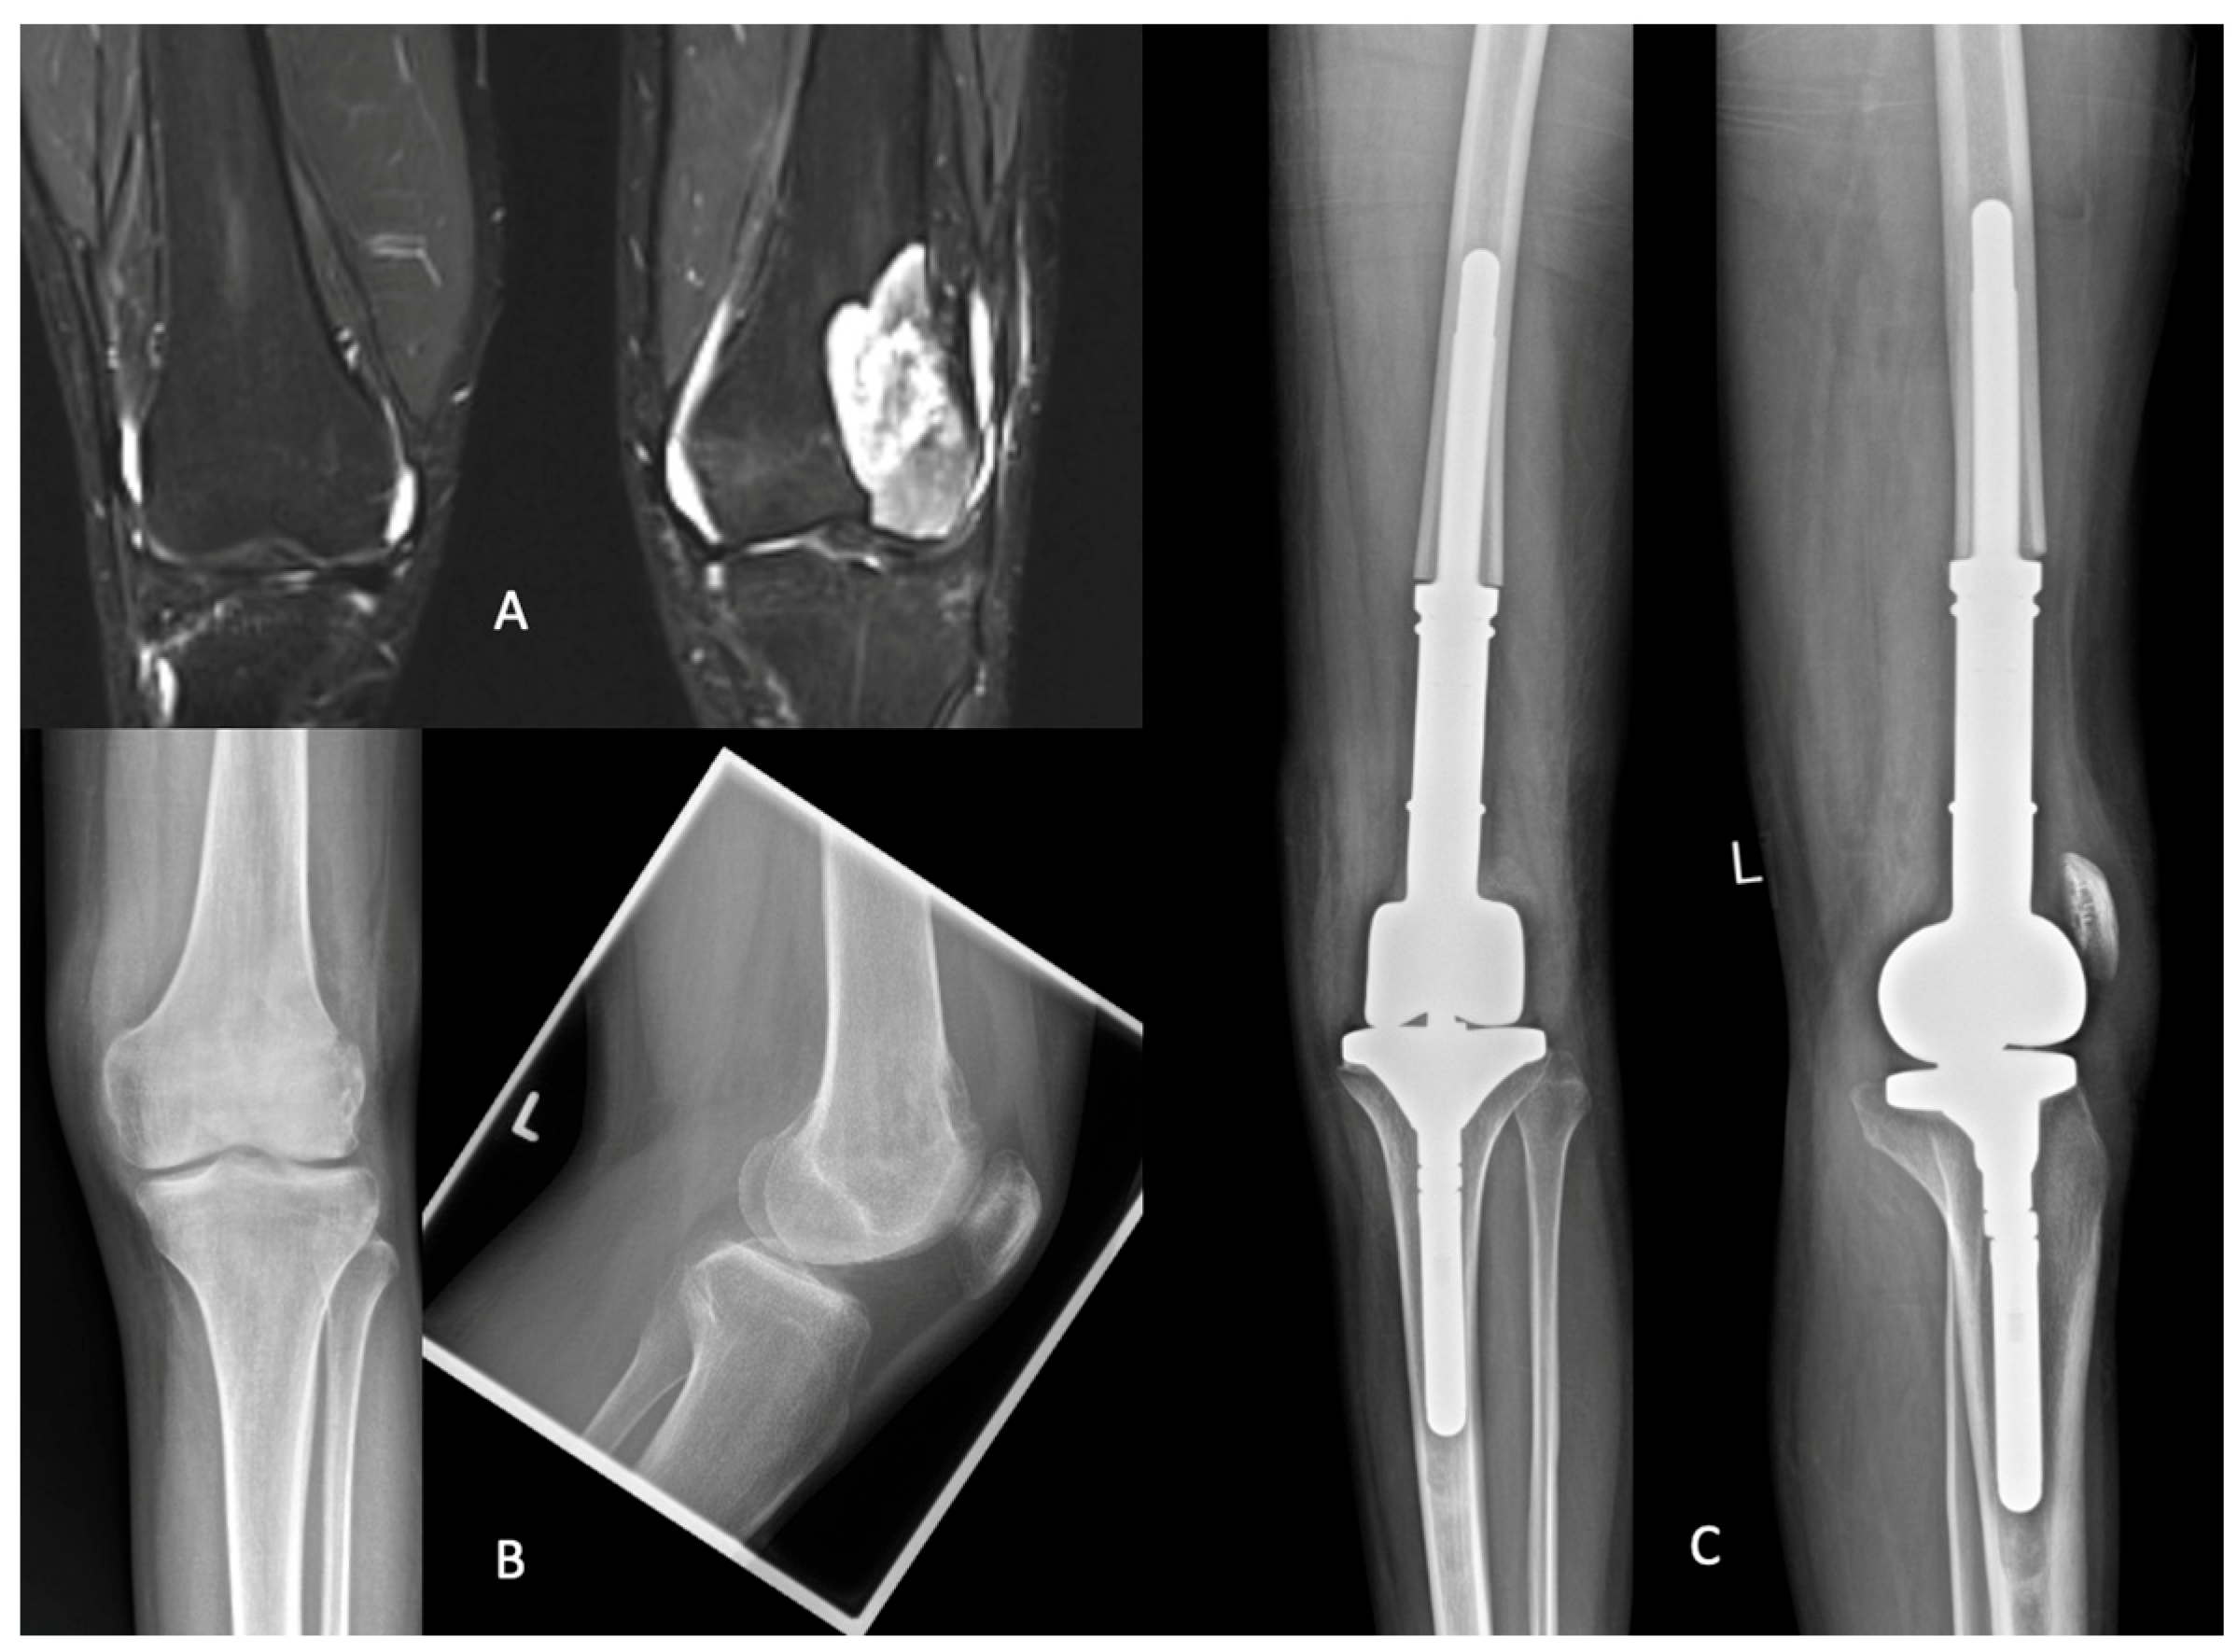

3.3.3. Example Case